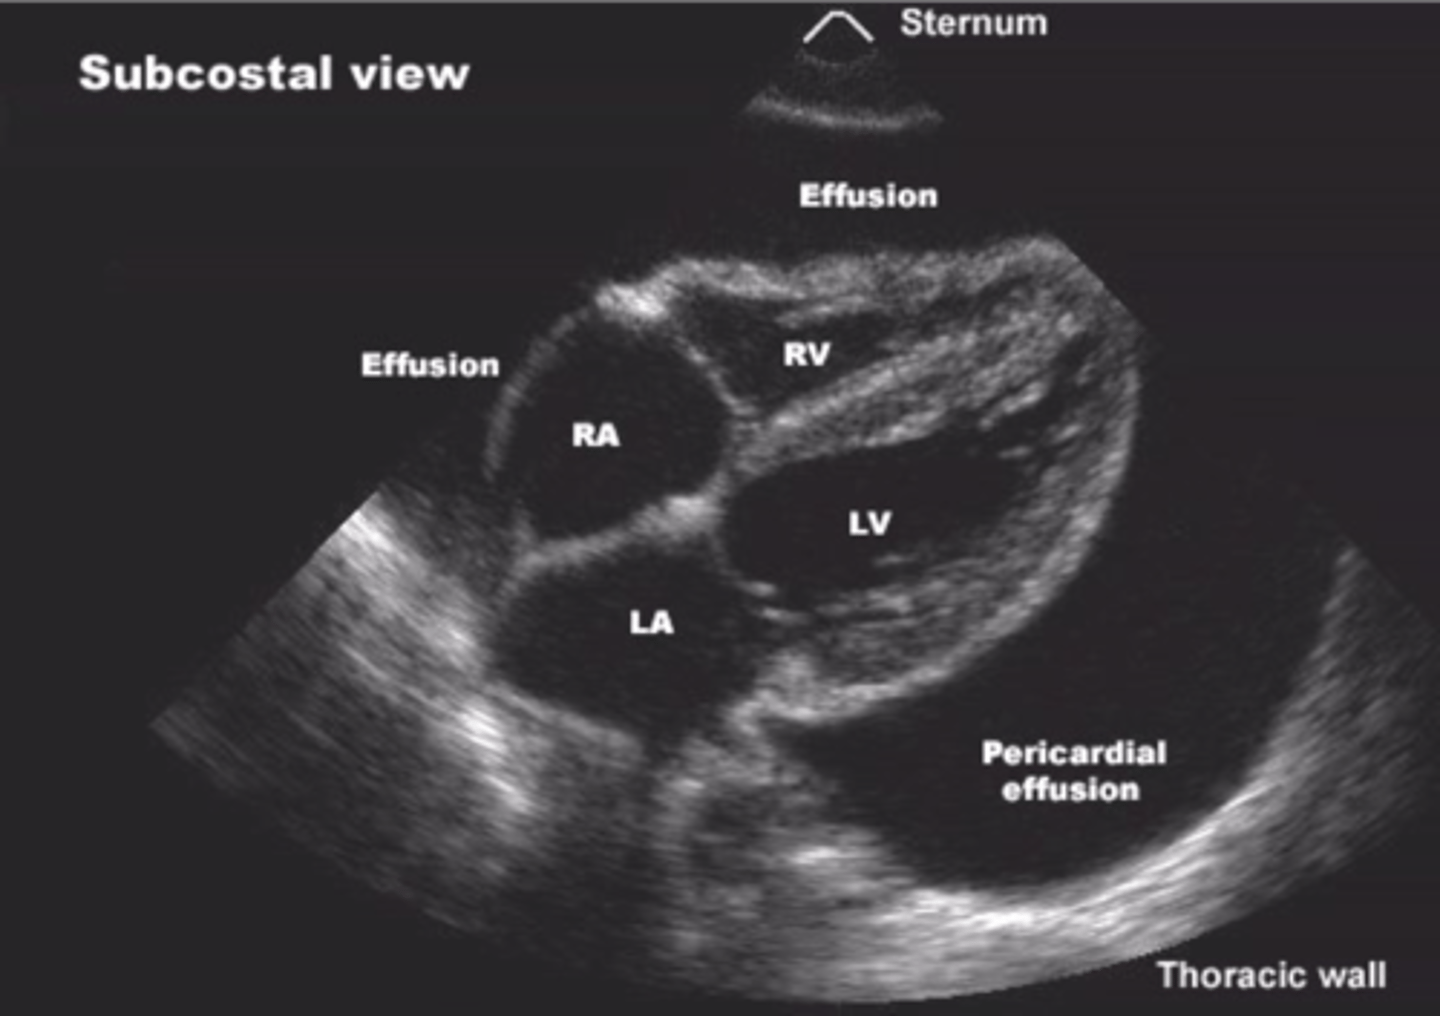

What are diagnostic ultrasounds used for?

View organs & evaluate motion (cardiology, OBGYN, GI, & vascular medicine)

Diagnostic ultrasound

Echoes of the US beam bounce off interfaces between tissues with different acoustic properties

-Sends high-frequency sound into patient & assesses strength & time of returning echoes

-Echoes caused by changes in density

What are ultrasounds used for?

Obstetrics, cardiology, vascular, abdominal

What's an echocardiogram used to evaluate?

Valves, pericardial fluid, pressures, wall motion, ejection fraction, & masses